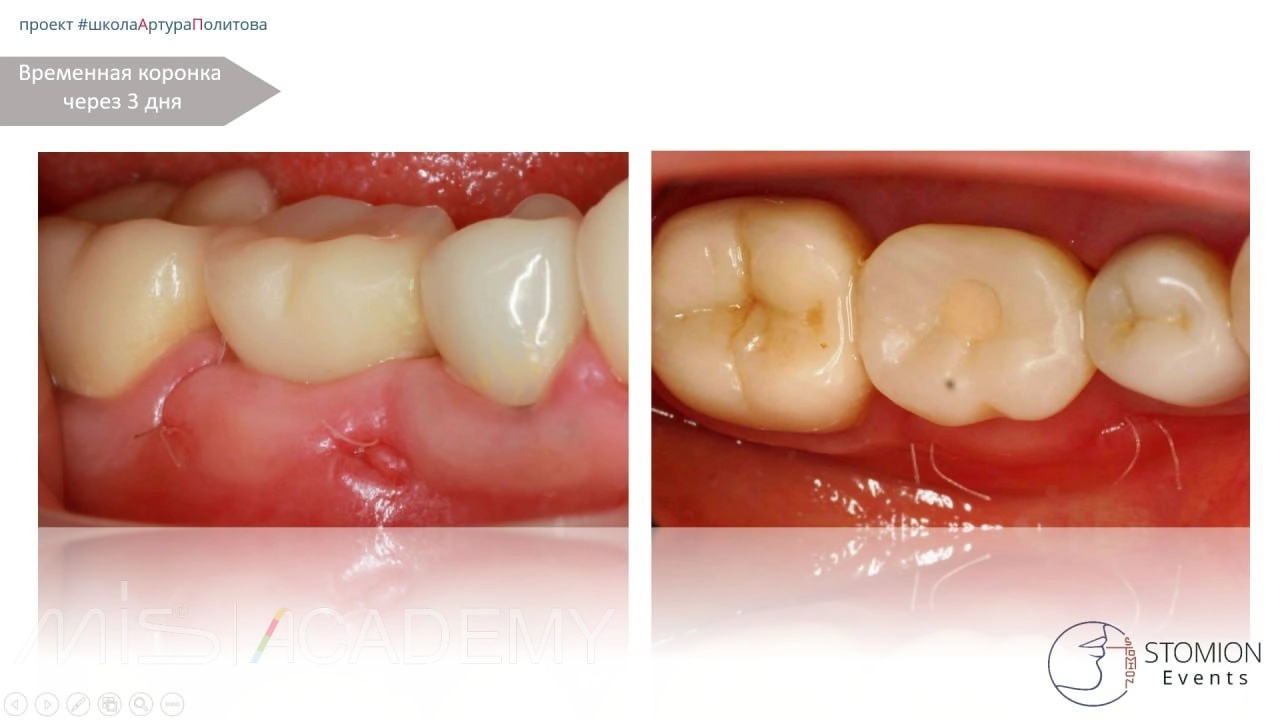

4. Через 3 дня изготовлена и зафиксирована временная коронка.